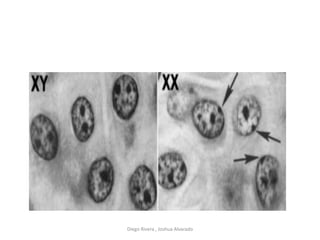

• DEFINA EL SEXO

• ORGANOS OBSERVABLES

Diego Rivera , Joshua Alvarado